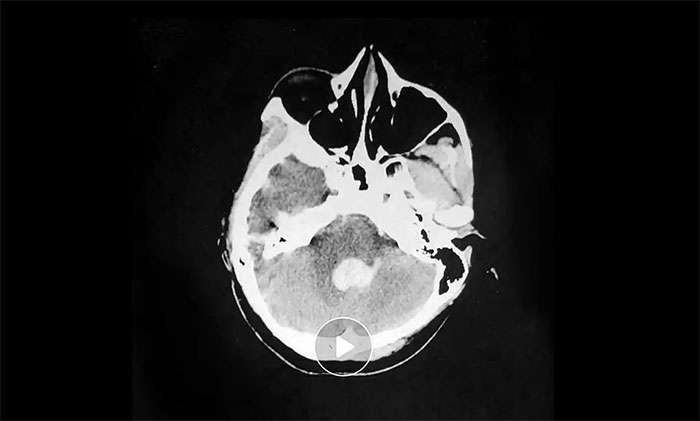

術(shù)后,在救治醫(yī)院進(jìn)行腦血管CTA檢查發(fā)現(xiàn):雙側(cè)大腦中動(dòng)脈近端狹窄,左側(cè)近乎閉塞,周圍有異常血管網(wǎng),診斷為“煙霧病”——這正是造成小雨突發(fā)腦出血的罪魁禍?zhǔn)住?/p>

“煙霧病”因顱底異常血管網(wǎng)在腦血管造影圖像上形似“煙霧”而得名,危害極大,既可造成腦出血,也可發(fā)生腦梗死,更嚴(yán)重者可同時(shí)發(fā)生腦出血和缺血梗死。尤其當(dāng)出血與缺血并存時(shí),治療過程將更為棘手。

▲ 異常血管網(wǎng)影像表現(xiàn)形似“煙霧”